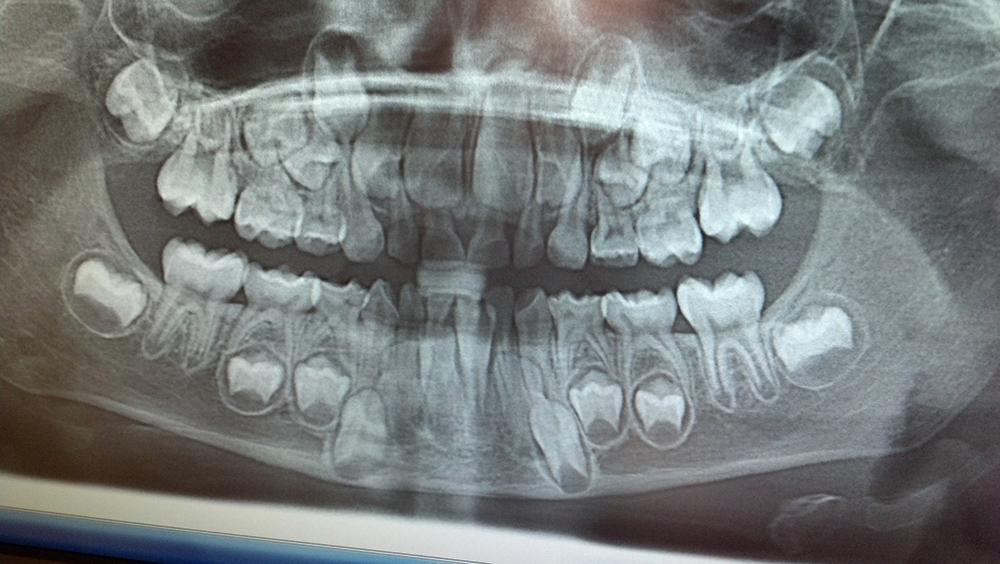

Outra forma de arrancar os dentes de leite é ir no dentista. É importante que até à ida do dentista, não tenhamos "invadido" a boca da criança, porque nessa fase da queda dos dentes de leite, qualquer dor que seja provocada pode traumatizar a criança, e ela não deixar que toquem mais na boca dela mesmo que seja para o seu bem (caso do dentista). Indo no dentista, ele poderá fazer um raio-X à boca da criança e perceber quais os dentes que estão prestes a cair, e aqueles os que estão nascendo. Em alguns casos irá aconselhar que sejam arrancados um ou dois dentes para que os definitivos possam nascer sem causar distúrbios na boca, para que o sorriso se mantenha direito.